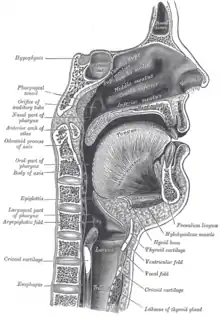

Mouth & Pharynx

Digestion starts in the oral cavity. Food is taken into the mouth; as it is masticated by the teeth, it is mixed with saliva from the parotid, sub-mandibular, and sublingual glands. Saliva contains amylase and lipase enzymes, which are mixed with the food. Because these enzymes are deactivated on reaching the stomach, salivary action is greater when food is more thoroughly masticated. When mastication is complete, the food is swallowed; this is a three-part process, but only the first part is under voluntary control. (see Motility). The epithelial lining of the mouth and pharynx is non-cornifed squamous epithelium.

Esophagus

The esophagus extends from the pharynx to the stomach and is about ten inches in length. It traverses three regional anatomical areas: the neck, the thorax, and the abdominal cavity. At the upper and lower ends of the esophagus the musclar layers act like sphincters; they are in tonic contraction, and are known as the esophageal and the cardiac sphincters. Although the esophagus is outside the abdomen, and thus does not have a serosal layer, it has the same basic layout as the rest of the system.

The epithelium of the mucosal layer is non-cornified stratified squamous epithelium. The lamina propria is not copious and contains aggregates of lymphoid tissue.

The oesophageal glands are scattered throughout the length of the esophagus and are located in the submucosa. There are also cardiac glands, which are similar in microscopic appearance to those in the stomach but have no enzymes in their secretions, at the proximal and distal ends of the esophagus. These glands are confined to the mucosal layer.

The longitudinal rugae disappear on swallowing. The sub-mucosal layer consists of loose fibrous tissue and elastic tissue that allow expansion.

No new digestive enzymes are added nor does absorption take place in the esophagus.